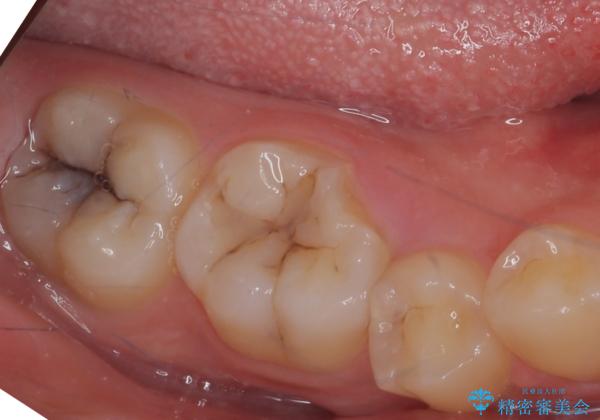

その際、舌側の歯の高さがなく歯肉に埋もれ気味だったっため、奥の親知らずをぬくついでに予め歯周外科処置(要は歯の周りの組織の手術という意味です)を行い、歯ぐきの高さを下げました。

右下7番の虫歯の範囲は咬合面だけだったため、詰め物(セラミックインレー)で治療しました。

下に親知らずがある場合、奥歯の高さを出す手術は親知らずを抜くのと同時に行うことができますので1度で大きく歯ぐきを下げることができます。